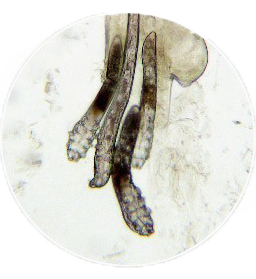

ㆍ頭髮檢查

用來檢查頭髮外觀是否有異常,及

是否受到黴菌感染。